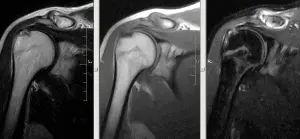

На зображенні: розрив сухожилля надостной м’язу.